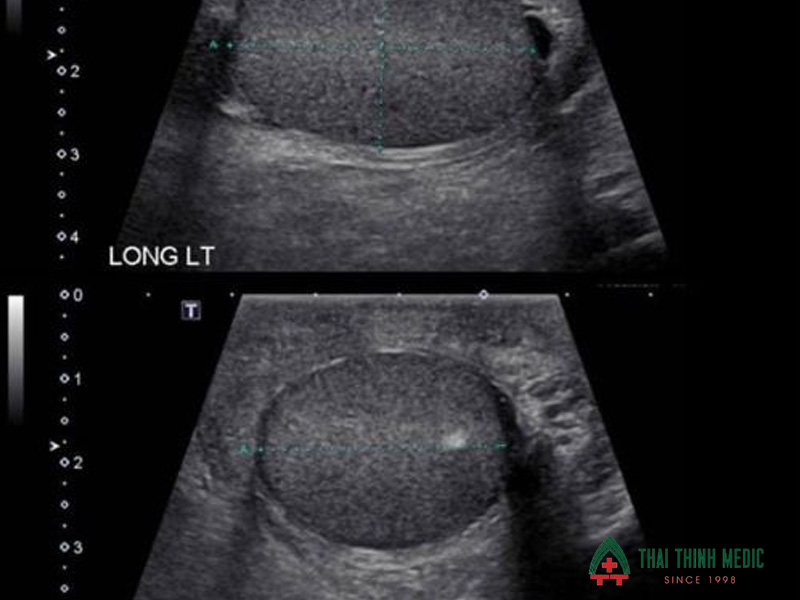

Siêu âm tinh hoàn và cơ quan sinh dục

Siêu âm tinh hoàn là phương pháp chẩn đoán hình ảnh giúp bác sĩ kiểm tra cấu trúc và tình trạng của các cơ quan sinh sản nam. Phương pháp này có thể phát hiện nhiều bất thường ảnh hưởng đến quá trình sản xuất tinh trùng, đặc biệt là các bệnh lý tại tinh hoàn hoặc bìu.

- Giãn tĩnh mạch thừng tinh là nguyên nhân phổ biến gây suy giảm chất lượng tinh trùng.

- Viêm tinh hoàn hoặc viêm mào tinh hoàn là tình trạng viêm nhiễm này có thể ảnh hưởng đến khả năng sản xuất tinh trùng.

- U hoặc khối bất thường tại tinh hoàn có thể ảnh hưởng đến chức năng sinh sản.

- Tắc nghẽn đường dẫn tinh dẫn đến tinh trùng yếu.

- Bất thường cấu trúc bìu hoặc tinh hoàn có thể ảnh hưởng đến môi trường phát triển của tinh trùng.

Siêu âm tinh hoàn